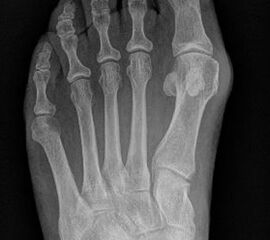

Abb. 7 a, b: Typ II Deformität mit prä- (a) und postoperativem Röntgenbild (b) mit K-Draht Osteosynthese und gleichzeitiger Hallux valgus Korrektur.